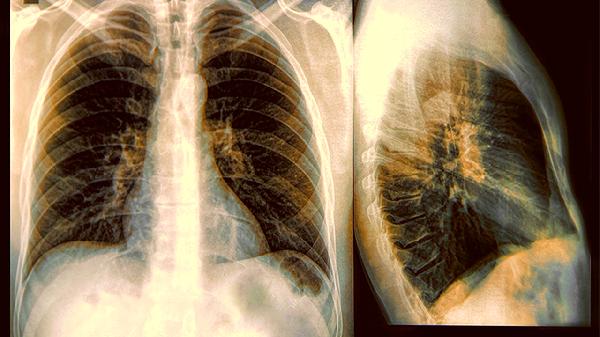

双腿出现这 3 个症状,可能是肺部已经癌变!千万别不重视!

走路时突然腿疼得像抽筋,爬楼梯时双腿发软使不上劲,甚至莫名其妙出现皮肤变色……这些看似普通的腿部问题,可能正在悄悄拉响肺部健康的预警。很多人以为腿和肺八竿子打不着,但身体这个精密的系统,往往用意想不到的方式发出求助信号。